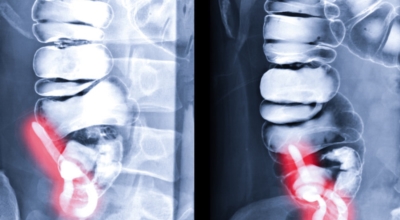

충수염은 통상적으로 맹장염이라고도 해요. 충수(Appendix)란 대장의 첫 부분에 붙어 있는 끝이 막힌 작은 관을 말해요. 급성 복통의 흔한 원인이며, 응급실에서 일반적으로 절제술을 시행하고 대부분이 잘 끝나게됩니다.

맹장염은 맹장 끝 충수돌기에 생기는 염증이라고 볼 수 있고, 보통 맹장염으로 알려져 있기는 한 개 실질적으로는 부위가 충수돌기이기 때문에 의학 용어로는 충수염이라고 부르는 단어가 더욱더 정확하다고 해요. 맹장염(충수염)은 한국 사람들이 수술을 진행하는 질병 5위라고 불릴 정도로 빈번히 발생하며 매년 약 10만 명 정도가 수술을 받듯이 흔히 생기는 질환입니다.

복통과 소화불량으로부터 시작하는 맹장염 초기 증상이 나타나는데 많은 분들이 소화기 계통 질환으로 오인해 약만 먹고 그냥 지나치는 경우가 많다고 해요. 대장이 시작되는 부위를 맹장이라고 하며 그 끝부분에 약 5~10cm 정도의 길이로 꼬리처럼 달린 구조물을 충수 또는 충수돌기라고 그러나, 일반적으로 말하는 맹장염은 이 충수가 막히거나 눌려서 염증이 발생해 통증이 생기게 되는데 심할 경우 터지는 경우가 나타나기도 해요.